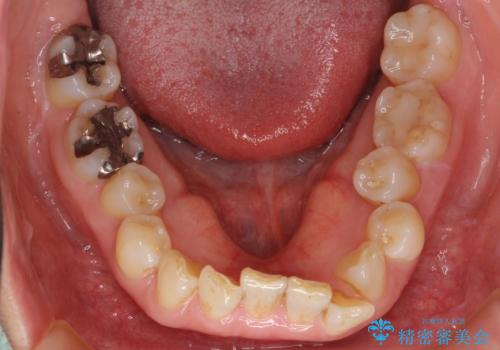

50代女性 インビザライン かみ合わせが深く、難しい症例

かみ合わせが深く、上の歯が咬みこんで下の歯にワイヤーがつけられない状態で、ワイヤー矯正はかなり難しい状態でした。

反対咬合や、すれ違い咬合もあり、大変難しいケースでしたが治療することができました。